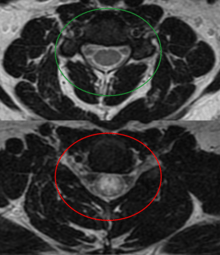

Longitudinally extensive transverse myelitis

A proposed special clinical presentation is the "longitudinally extensive transverse myelitis" (LETM) which is defined as a TM with a spinal cord lesion that extends over 3 or more vertebral segments.[12] The causes of LETM are also heterogeneous[13] and the presence of MOG auto-antibodies has been proposed as a biomarker for discrimination.[14]